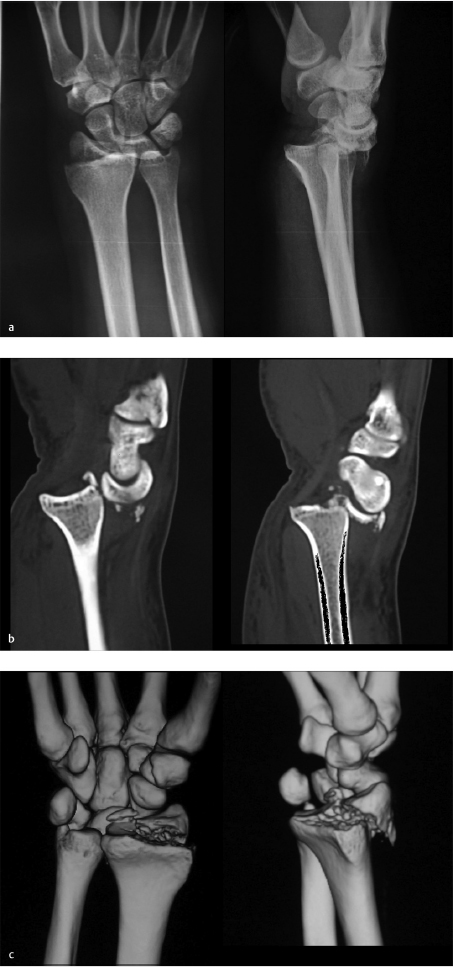

A 30 y/o male sustained a fall from a height and presented with right distal radius fracture. PA and lateral radiographs revealed a complex radiocarpal fracture-dislocation of his right wrist (► Fig. 44.3). Sagittal, two-dimensional CT views demonstrate the very small shearing fracture of the dorsal aspect of the distal radius with dislocation of the carpus (► Fig. 44.3).

Three-dimensional CT reconstructions show the volar rim of the radius to be intact with the dorsal small shearing fracture fragments (► Fig. 44.3). Also seen in all the preoperative images is the radial styloid fracture. Notice the horizontal fracture line involving the entire scaphoid fossa and continuing to the dorsal cortical rim. Operative fixation was recommended. A standard dorsal approach to the wrist was used, with a longitudinal incision over distal radius and radiocarpal joint in line with the 3rd metacarpal. The extensor pollicis longus tendon was mobilized from the 3rd dorsal compartment and the tendons of the second and fourth dorsal compartment were retraced to gain exposure (► Fig. 44.4). The dorsal small rim and the radial styloid fractures are clearly visualized. Usually the capsule is torn (► Fig. 44.4), but if it is intact, a dorsal arthrotomy is made parallel to the dorsal rim to inspect the articular surface and look for any associated carpal injury. At this point, carpus is reduced and fixation is started with the less comminuted fracture fragment. In this case, a 0.062 smooth K-wire was used for provisional fixation of the radial styloid fracture, and articular reduction was also confirmed using intraoperative fluoroscopy (► Fig. 44.4). If dorsal rim fragments are adequately large, provisional fixation can be obtained with K-wires. If they are too small, they can be held with suture anchors or transosseous sutures. Low-profile dorsal-distal radius plates were then used for fragment-specific fixation (► Fig. 44.5). Radial column plate and 2.4 mm dorsal plate were used. Capsule was repaired using resorbable suture (► Fig. 44.5). Follow-up at 8 months showed excellent function with some loss of wrist extension and flexion (► Fig. 44.6). Many plates are available for these fractures. The most recently designed plates have variable angle locking screws. The dorsal plate should be applied as distally as possible. These plates might need some contouring to fit the distal radius metaphysis and the radial styloid.